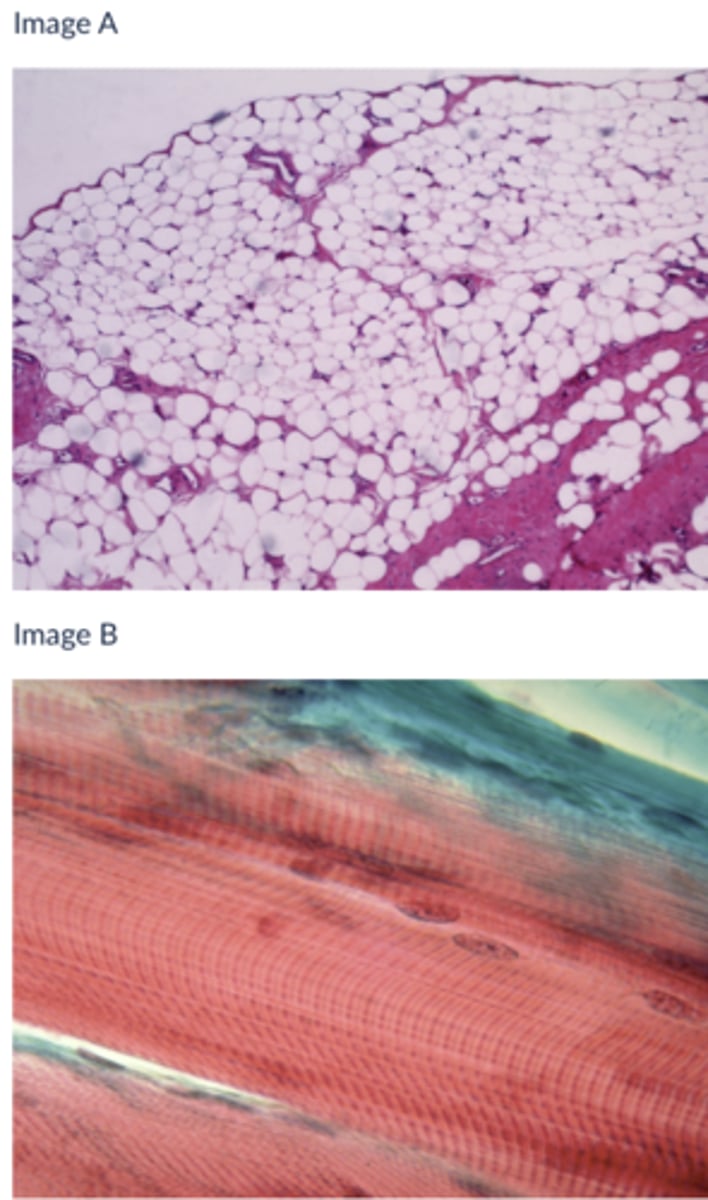

skeletal tissue

Which type of striated muscle tissue is presented in the following image:

cardiac muscle tissue

Which type of striated muscle tissue is presented in the following image:

A

Which of the following tissues is likely responsible for secretion or absorption

Image A

Image B

Neither

Both

B

Which of the following tissues is contractile?

A

B

Both

Neither

skeletal muscle

Which of the three muscle tissue types is presented in the following image:

cardiac

Which of the three muscle tissue types is presented in the following image:

A

Which of the following tissues is likely responsible for protecting the surface of the body from friction

A

Which of the following tissues stretches to accommodate increases in pressure: